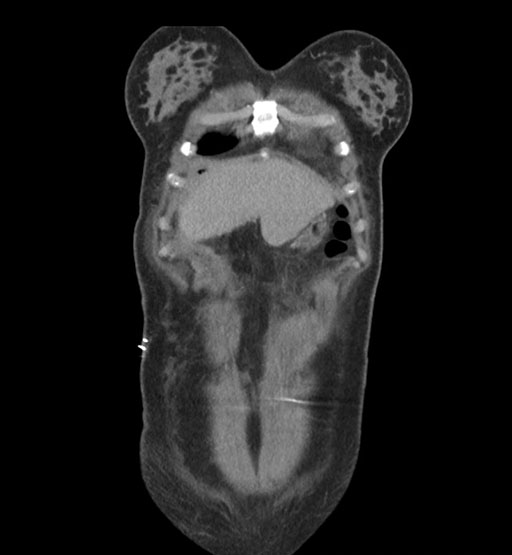

Axial Arterial

Axial Venous